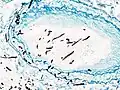

![]() Гистопатологическая картина инвазивного аспергиллёза лёгких у пациента с интерстициальной пневмонией. Аутопсийный материал. | |

При микроскопии аспергиллы надёжно выявляются посредством окраски материала серебром, например по Гомори-Гроккоту[5]. При окраске стенки грибов приобретают тёмно-серый цвет. Диаметр гиф аспергилл варьирует от 2,5 до 4,5 мкм. Гифы септированы[6], однако в некоторых случаях это неочевидно и их возможно принять за зигомицеты[5]. Гифы аспергилл имеют дихотомическое ветвление, преимущественно под острым (около 45°) углом[5].